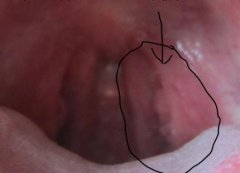

尖锐湿疣的治疗包括两个方面,一是除疣体,二是根治复发。由于目前尚无一种方法可以彻底根除人乳头瘤病毒,故在临床上大多数采用多种方法联合的综合疗法。因各种治疗方法疗效个体差异很大,一部分人单一去除疣体后不用其他特殊治疗即可达到治愈后不再复发;另一部分人尽管再去除疣体后加用一些全身性综合治疗方法等,CA仍反复发作,长时间不愈还有一小部分人可以发展为巨大CA,甚至发展为肛门生殖器部位的恶性肿瘤。

比较常用的尖锐湿疣的治疗方法有局部药物治疗适用于男女外生殖器部位的尖锐湿疣,且疣体不大的尖锐湿疣治疗,这种治疗方法方便,患者可在家中自己治疗,但使用方法要得当,且需注意药物的副作用和不良反应。多数尖锐湿疣可采用物理治疗,但激光、冷冻、微波等物理治疗虽可快速祛除疣体,但却不能有效消除HPV亚临床感染和潜伏感染。外科治疗适用于较大的疣体,手术切除效果较好,但手术切除治疗创面大,术后易形成瘢痕。